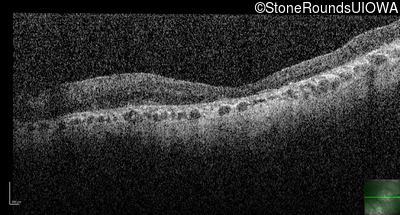

Optical Coherence Tomography - Right - Hand Motion 1' sc

Exemplar / OCT Stack